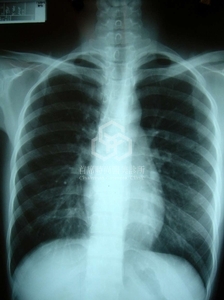

這是乳房不對稱最明顯的胸闊主因, 通常整形外科醫師不太認真看消費者的胸部X光, 畢竟美容刀誰管那麼多, 交給麻醉科醫師看就好, 甚至兩個人都不看.

結果其實它透露出許多寶貴的訊息, 非常可惜.

整形外科醫師不注意, 不發表這類案例, 但是骨科醫師 Normelli H. et al等人於1986年寫了一篇標題為: "The symmetry of the breasts in normal and scoliotic girls."的醫學論文. 這是一篇重要的paper, 雖然不是整形外科醫師寫的, 但是他們發現對於右脊柱側彎的患者(right thoracic idiopathic scoliosis), 左邊乳房通常比右邊大.

2004年 Sanders R. 才於PRS期刊上發表"Frequently unrecognized causes of breast asymmetry Plastic & Reconstructive Surgery."小小短短不起眼的通訊文章(communication)裏, 提醒大家注意這種脊柱側彎的可能.